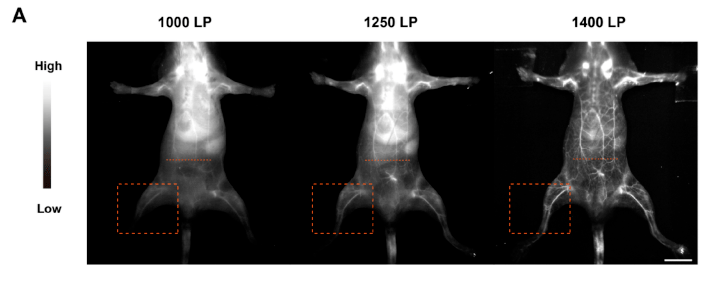

【案例2】近红外二区成像在不通波长下成像比较

通过尾静脉注射PBS溶液中的NM-NPs雌性BALB/c小鼠。用1000LP、1250LP、1400LP滤光片进行160mW cm−2808 nm激光激发,当波长在1000~1400 nm之间变化时,血管的清晰度明显提高,1400LP滤光片NIR-II荧光成像的空间分辨率明显提高,清晰度显著提高。